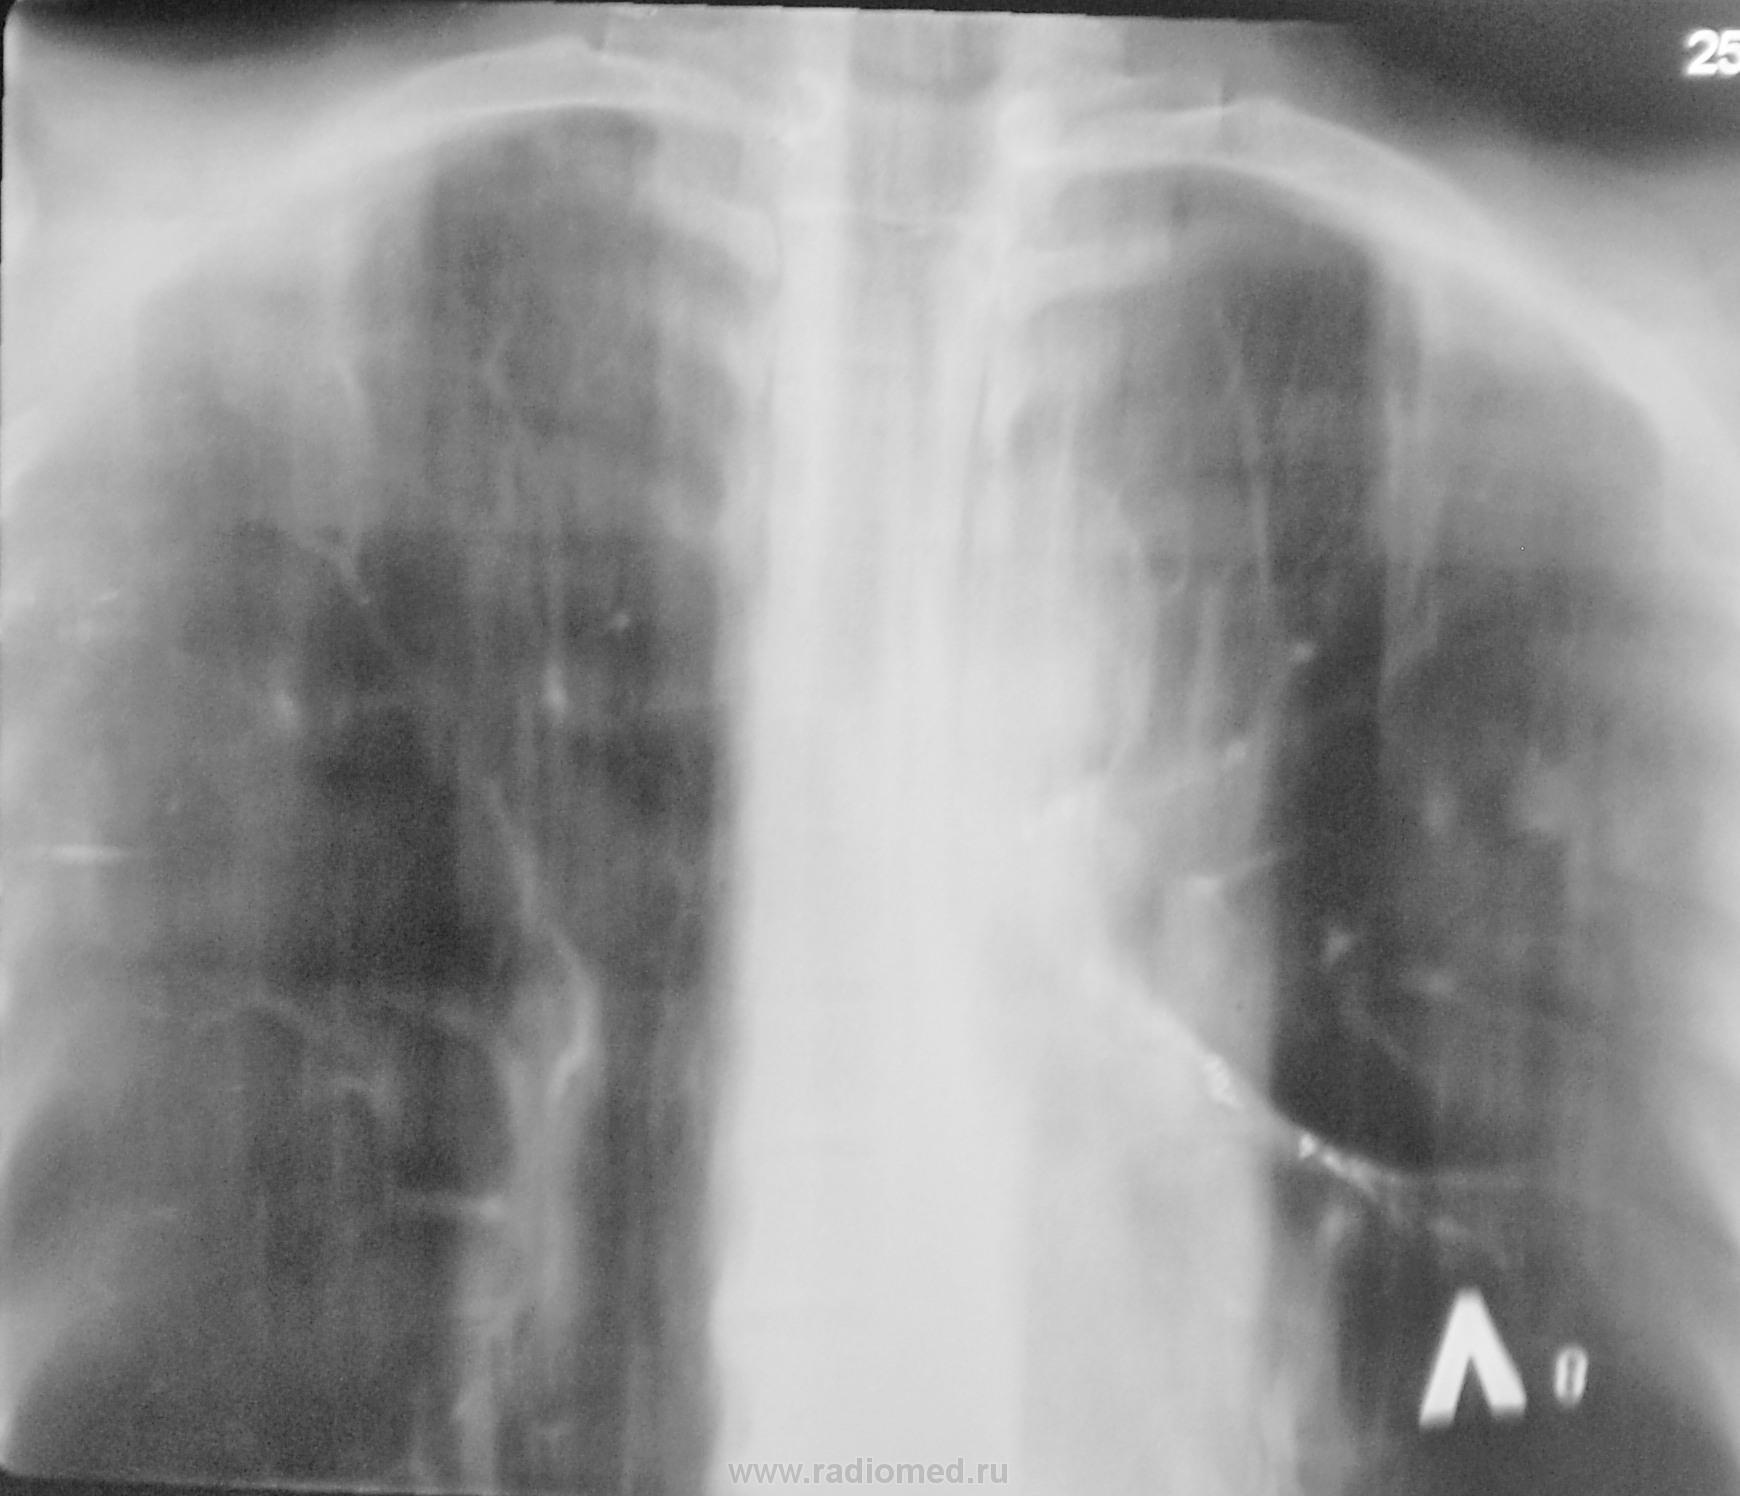

Договорена консультация и госпитализация в ОПТД. По просьбе коллеги фтизиатра делам томограммы в прямой проекции.

Коллега фтизиатр находится в растрепанных чувствах, настаивает на томографии в прямой проекции.